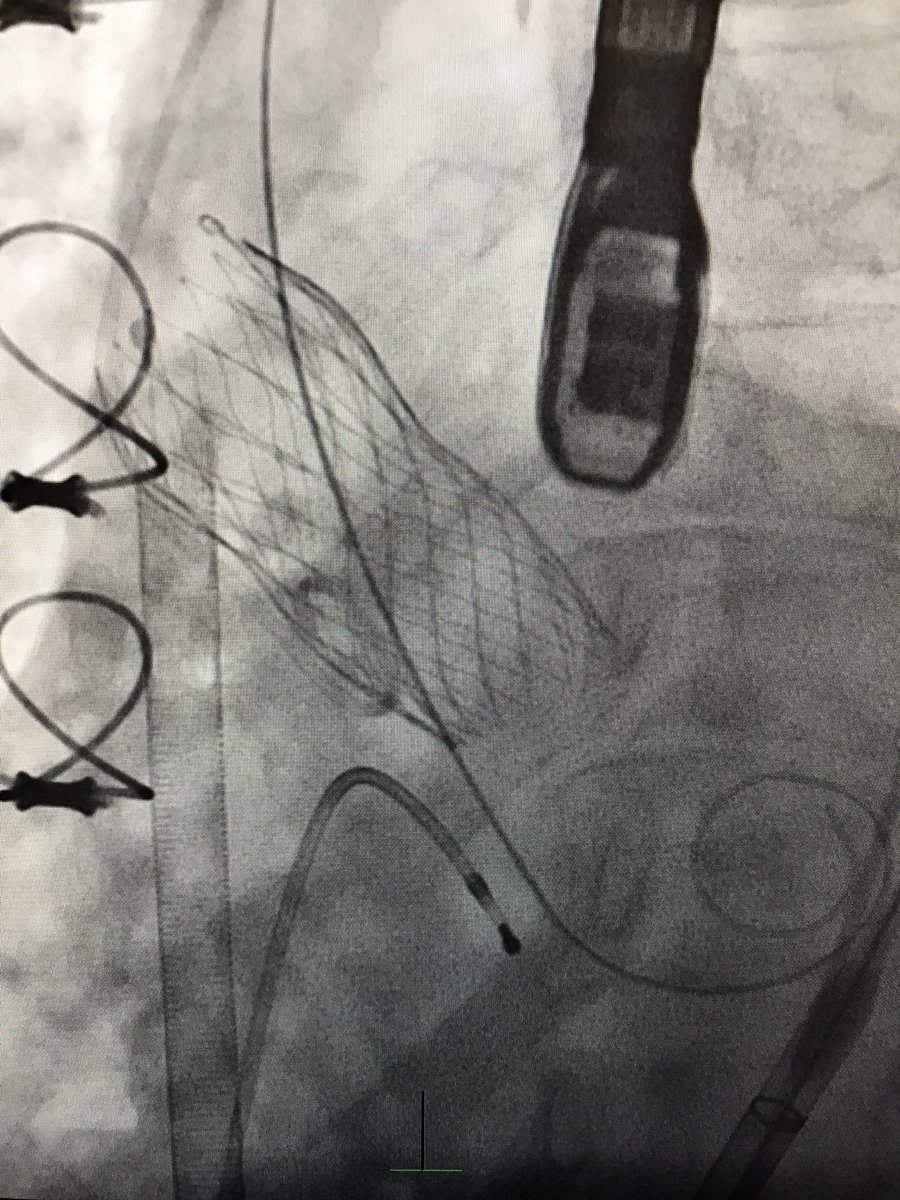

#ViVTAVR for degenerated Freestyle w/severe AR, EF 25%, #TranscavalTAVR, on-pump, no PVL post, 👍 @JasonFoerst ! #CarilionStructural #SHIP